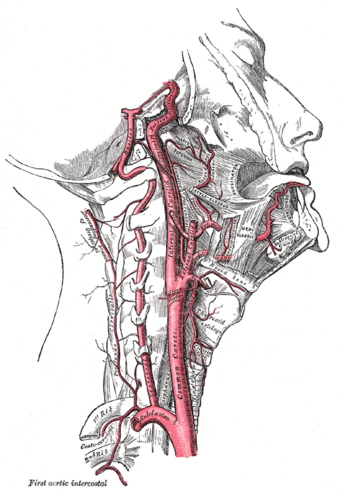

Arteries of the neck. The internal carotid arteries arise from the common carotid arteries - labeled Common caroti on the figure. | |

يُشكل الشريان السباتي والوريد الوداجي مع العصب المبهم حبلاً مشتركاً يصل عبر الرقبة إلى الرأس، ويحاط هذا الحبل بنسيجِ ضامِ يجري بين عضلات الرقبة. هذا الحبل يمر في الجزء الأسفل من الرقبة تحت العَضَلَةُ القَصِّيَّةُ التَّرْقُوِيَّةُ الخُشَّائِيّة (باللاتينية: Musculus sternocleidomastoideus)، ليصل في وسط الرقبة إلى مثلث عضلي بين العَضَلَةُ الكَتِفِيَّةُ اللَّامِيَّة (باللاتينية: Musculus omohyoideus) والعضلة القَصِّيَّةُ التَّرْقُوِيَّةُ الخُشَّائِيّة والعضلة ذات البطنين (باللاتينية: Musculus digastricus) هذا الحبل يمكن تحسسه بالإصبع من خلال تحسس نبض الشريان السباتي هناك[4].

هناك شريانان سباتيان، السباتي الأيمن والسباتي الأيسر، حيث ينبع السباتي الأيمن من الجِذْعُ العَضُدِيُّ الرَّأْسِي بينما ينبع الشريان السباتي الأيسر من الشريان الأبهر مباشرة، يسمى الشريان السباتي هنا الشريان السباتي الأصلي. السباتي الأصلي ينقسم إلى فرعين الشريان السباتي الظاهر و الشريان السباتي الغائر.

ينبع الشريان السباتي الأصلي الأيمن من الجذع العضدي الرأسي بينما ينبع الشريان السباتي الأصلي الأيسر مباشرةً من الشريان الأبهر بالإتجاه القِحْفي لينقسم - دون أن يُعطي فروعاً قبل ذلك - إلى فرعية الرئيسين الظاهر والغائر. قبيل الانقسام يتوسع ليشكل ما يسمى بالجيب السباتي (باللاتينية: Sinus caroticus). يحوي الجيب السباتي على مستقبلات الضغط إنگليزية: Baroreceptor ومجسات الضغط الجزئي للأكسجين فيما يسمى الكُبَّةُ السُّباتِيَّة (باللاتينية: Glomus caroticum)، والذين يلعبون دوراً في تنظيم ضغط الدم وتنظيم أكسدة الدم.

هو الفرع الخارجي (خارج الجمجمة) للشريان السباتي، وتنبع منه شريانات لتروية الرقبة والوجه والرأس خارج الجمجمة (عضلات وجلد وغدد ... الخ).

ووظيفتها جميعاً تزويد الوجه وأجزاؤه والأجزاء خارج الجمجمة من الرأس، والرقبة بالدم.